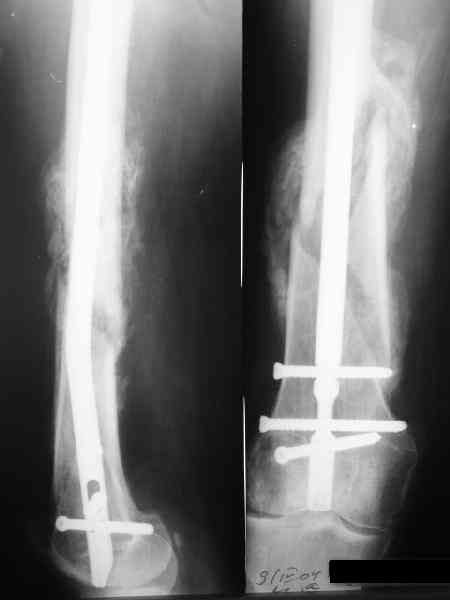

Спицы оставлять не надо. Надо их убрать, но перед этим ввести винт-poller. Такая необходимость возникает в редких случаях, когда можно ожидать смещения длинного отломка. Спицы из короткого отломка после введения запирающих винтов можно удалять без риска смещения.

В приложении пример, дистальный отломок пружинил кзади. Два винта потому, что первый оказался чуть кпереди и не упирался в гвоздь.